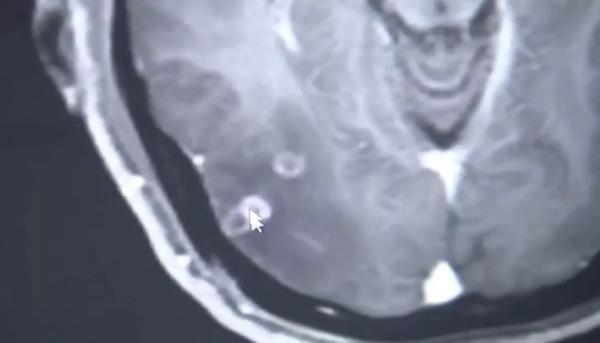

اكتشف رجل في الصين كان يشكو من الصداع والنوبات أكثر من 700 دودة شريطية في جسده بما في ذلك دماغه بعد تناول لحم ملوث.

وفحصه الدكتور وانغ جيان رونغ، من قسم الأمراض المعدية، وشخص إصابته بداء الشريطيات، ووجد أكثر من 700 دودة شريطية في جسمه.

وذكر الدكتور وانغ أن العدوى أضرت بالفعل بالمريض. ووفقاً لمنظمة الصحة العالمية، يتسبب بيض الدودة الشريطية في الجهاز العصبي المركزي، في أعراض عصبية للمريض، بما فيها نوبات الصرع.